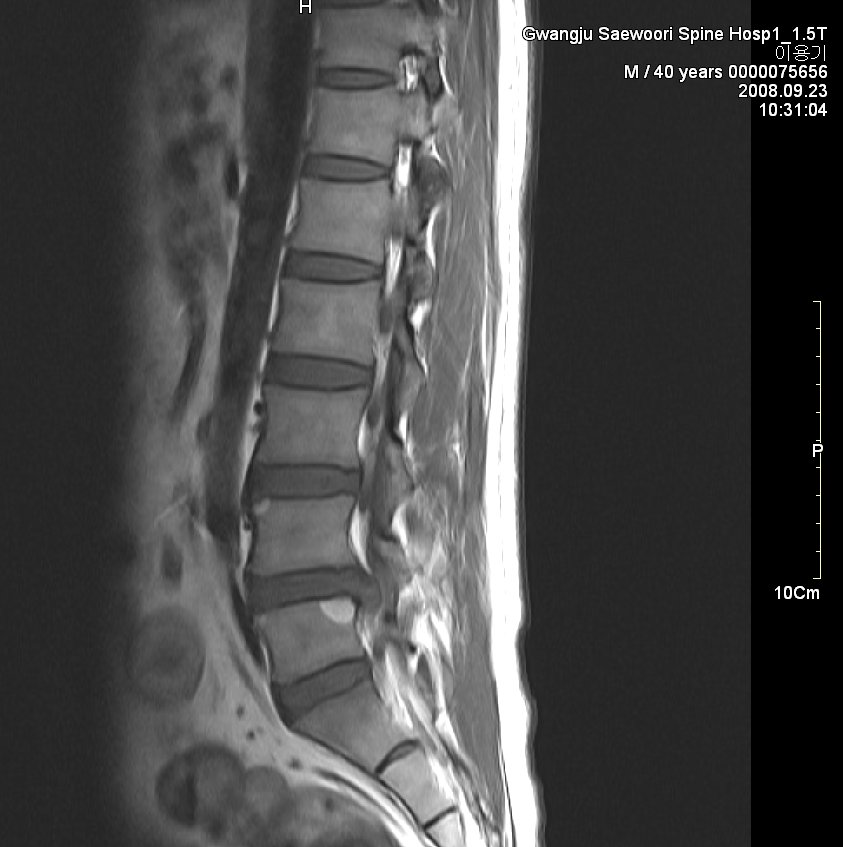

그림. sequestration사진. 월산동 남편 mri

그림. 흡수된 사진

symptom : local low back pain, lt buttock pain, lt leg radiating pain 허리에서 엉덩이 종아리까지 쑤시고 애림. 야간에는 통증으로 잠을 못 이룸.

sign : l5 sensory impairment, motor nerve intact(manual muscle powr test - nonspecific), dtr(++/++)

evidence : l-spine mri 사진

치료과정

침상안정 3일, 3일동안 허리 얼음찜질 1시간 30분씩 하루 5회 시행,

제가 2년 전 월산원광한방병원에서 치료한 환자 사진입니다. 수술을 위주로 치료하는 의사가 판단하기에 황당하게 보일지 모르겠습니다. 하지만 이 환자는 현재 가끔 골프도 치면서 허리디스크를 앓기 전보다 더 건강한 허리를 가지고 살아가고 있습니다.